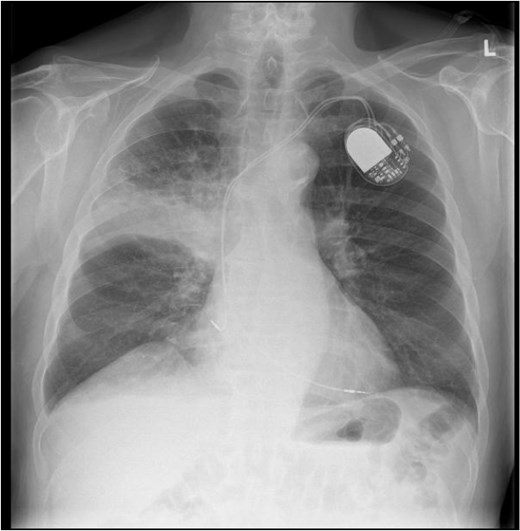

This 78-year-old man initially presented with a chest infection in October 2024, where a chest X-Ray (CXR) showed right upper lobe (RUL) consolidation accompanied by a pleural effusion (Fig. 1). He had no other symptoms, including haemoptysis, shortness of breath, fever, anorexia, or weight loss. A follow-up computed tomography (CT) chest 6 weeks later revealed a large endobronchial lesion in the right main bronchus, resulting in consolidation and partial collapse of the RUL (Figs 2 and 3). He went on to have a positron emission tomography (PET) scan (Fig. 4), CT head, bronchoscopy, and endobronchial ultrasound (EBUS). Imaging revealed a 3.8 cm lesion in the right upper lobe bronchus, which was mostly occluded. The biopsies showed evidence of a myoepithelial carcinoma, a rare pulmonary neoplasm.

CXR showing right upper lobe consolidation with a small right pleural effusion (dual lead pacemaker noted).